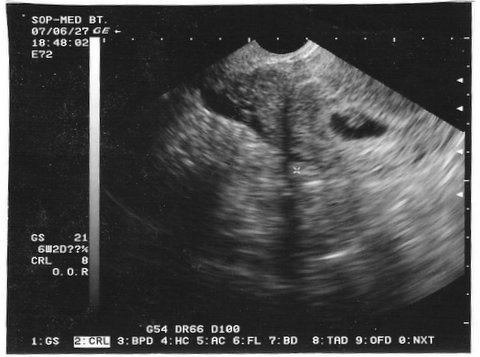

6+2 egy baba és szívhang 7mm:

7+2 babám már 12mm:

Jajj a második nagyon életlen lett.De annyi van ráírva,hogy 28,8 mm-es petezsák és 7+2 a kor. :D

Milyen szépen növöget a babócád. Olyan jó ilyen képeket látni. Az első kép hány hetesen készült? A 7,1 mm a képen a petezsák mérete?

Igen az a petezsák mérete,de mint Pandinak is írtam sajnos nem tudom mekkora a baba. :roll:

CRL 5 mm! (azaz nőtt az előző 1 mm óta). És jó életjeleket talált a doki, azaz dobogott a szive. Lányok én elsírtam magam ott, meg utána is amikor kijöttem a vizsgálóból. Azt mondta, hogy 6 hetes terhesség.

A szívhang a 6. hét elején már van persze nem mindenkinél de nekem 6+2 már volt szívhang és 7mm baba. Örülök hogy minden rendben van én is sírtam a szívhangnál :wink: